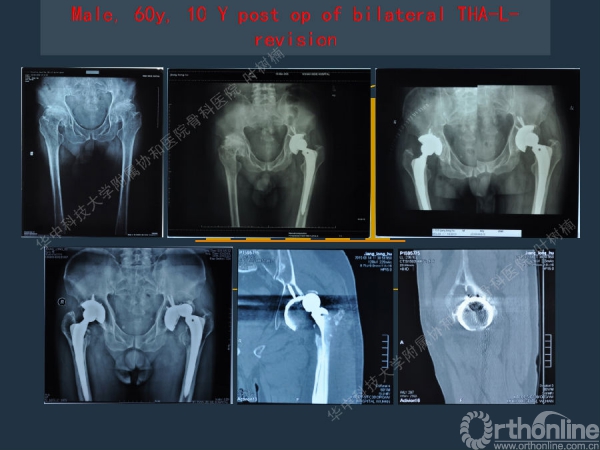

股骨侧翻修

髋臼缺损的处理